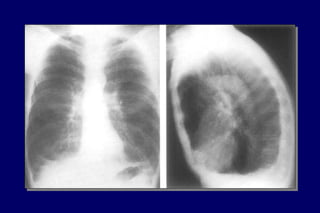

Radiografia

de tórax

Excluir outras

doenças

Bolhas

Hiperinsuflação

DIAGNÓSTICO História Exame físico Normal / quase Hiperinsuflação Murmúrio vesicular diminuído Sinaisde cor pulmonale mMRC-CAT Radiografia de tórax Excluir outras doenças Bolhas Hiperinsuflação Tabagismo Tosse Dispnéia Sibilos Exposição